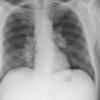

Lymphoma -Mediastinal and left axillary nodes

Date: 04/01/2014

Views: 2997